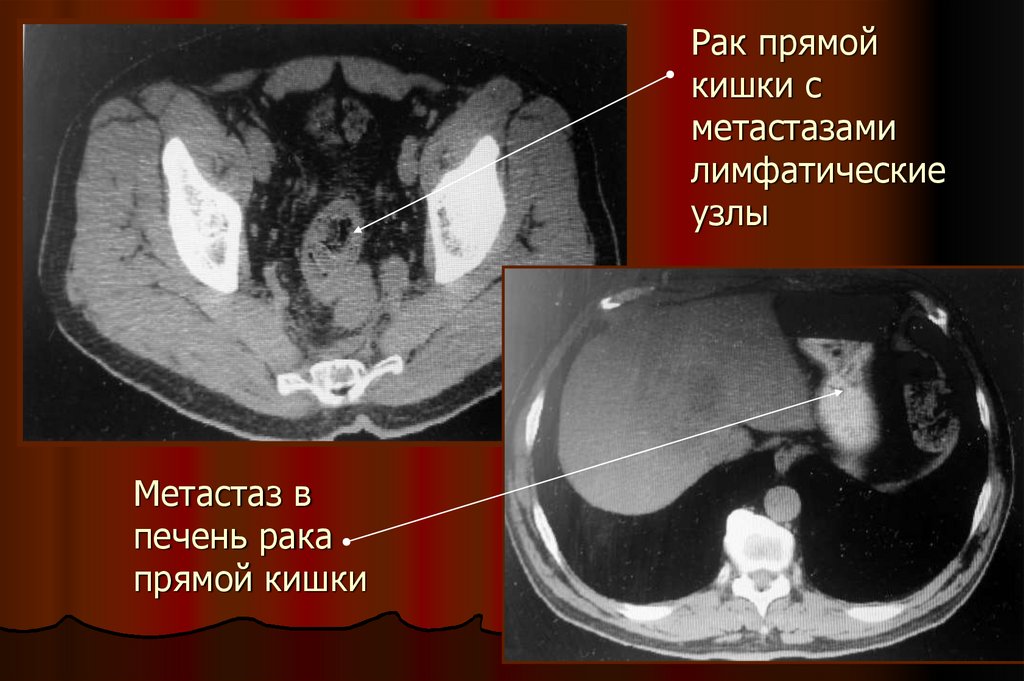

Рак прямой кишки с метастазами лимфатические узлы

24. Рак прямой кишки с метастазами лимфатические узлы

Метастаз в

печень рака

прямой кишки